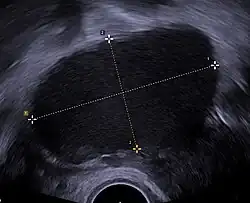

| Transvaginal ultrasonography showing a 67 x 40 mm endometrioma as distinguished from other types of ovarian cysts by a somewhat grainy and not completely anechoic content. | |